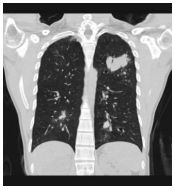

4. 39 y/o female, productive cough for 2 months